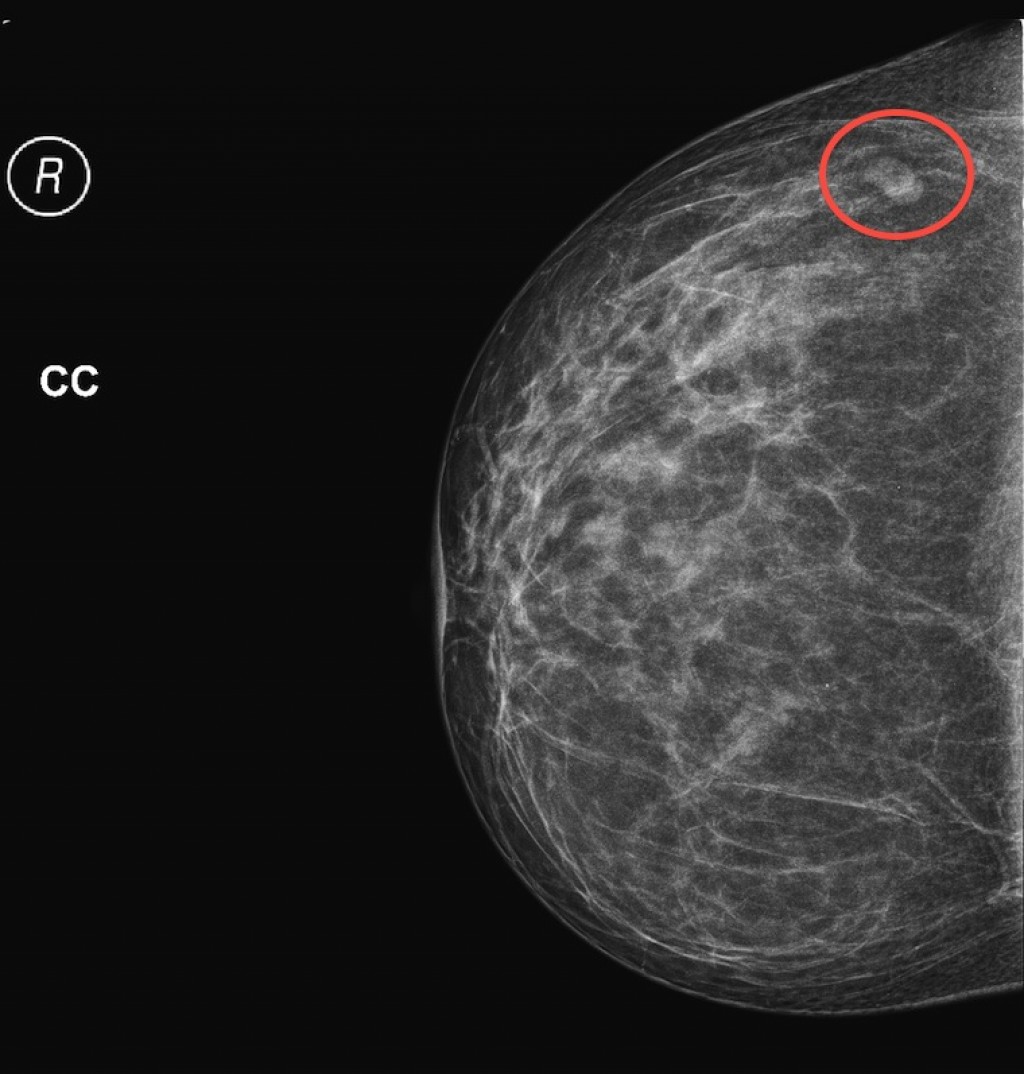

Фиброаденома молочной железы - доброкачественное образование, которое часто встречается у женщин. Оно может быть обнаружено при помощи различных методов диагностики, включая маммографию. Ниже представлены фотографии, помогающие понять, как выглядит данное заболевание.

Опухоль на снимке маммографии

Маммография и ее роль в диагностике фиброаденомы молочной железы

Маммография - это рентгенологическое исследование молочных желез. Оно позволяет выявить различные изменения в тканях, включая фиброаденому. На маммограммах можно увидеть структурные особенности опухоли и отследить ее динамику во времени.